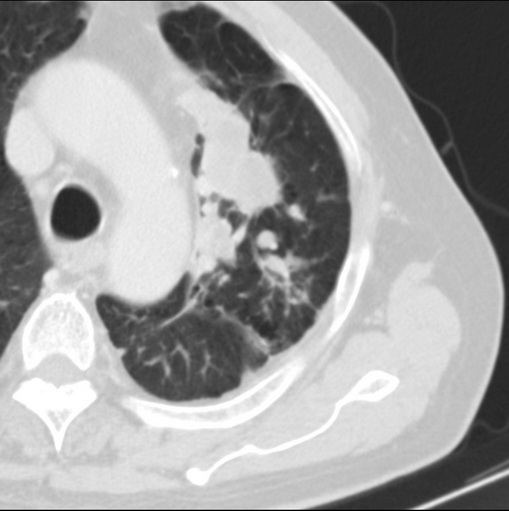

男性患者 81岁 咳嗽 咳痰 咯血

左肺中心型肺癌并:1.左肺阻塞性肺炎;2.纵隔淋巴结肿大;

强化较典型,左上肺癌并纵膈淋巴结转移;左上肺结核并空洞形成;胸膜增厚.

考虑左上肺癌并阻塞性肺炎,左肺转移、左肺门及纵隔淋巴结转移。

肿块贴近左肺门,包绕左上肺动脉,形态不规则。肿块增强扫描中度强化。纵膈内主动脉弓左旁间隙、气管隆突前、下间隙见多枚淋巴结影。综上考虑左侧中央型肺癌可能性大。图片没有完整上传,尤其是左肺上叶支气管分支层面没有上传,因此不好判断是叶支气管中断还是段支气管中断。另外,下图红色部分所示是“黏液支气管征”吗?